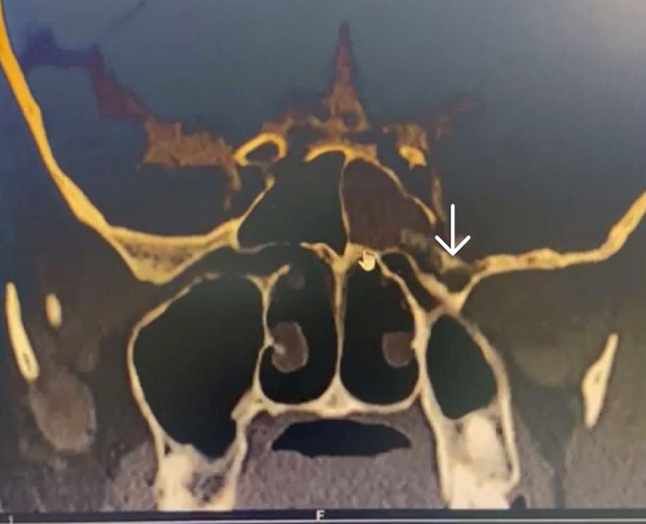

CT cisternography revealed thinning and erosion of the left cribriform plate posterior to the crista galli (figure 1) and the lateral recess of the left sphenoid (figure 2).

Figure 2. CT cisternography -arrow showing thinning and erosion of the lateral wall of sphenoid sinus above vidian-rotundum line with csf leakage